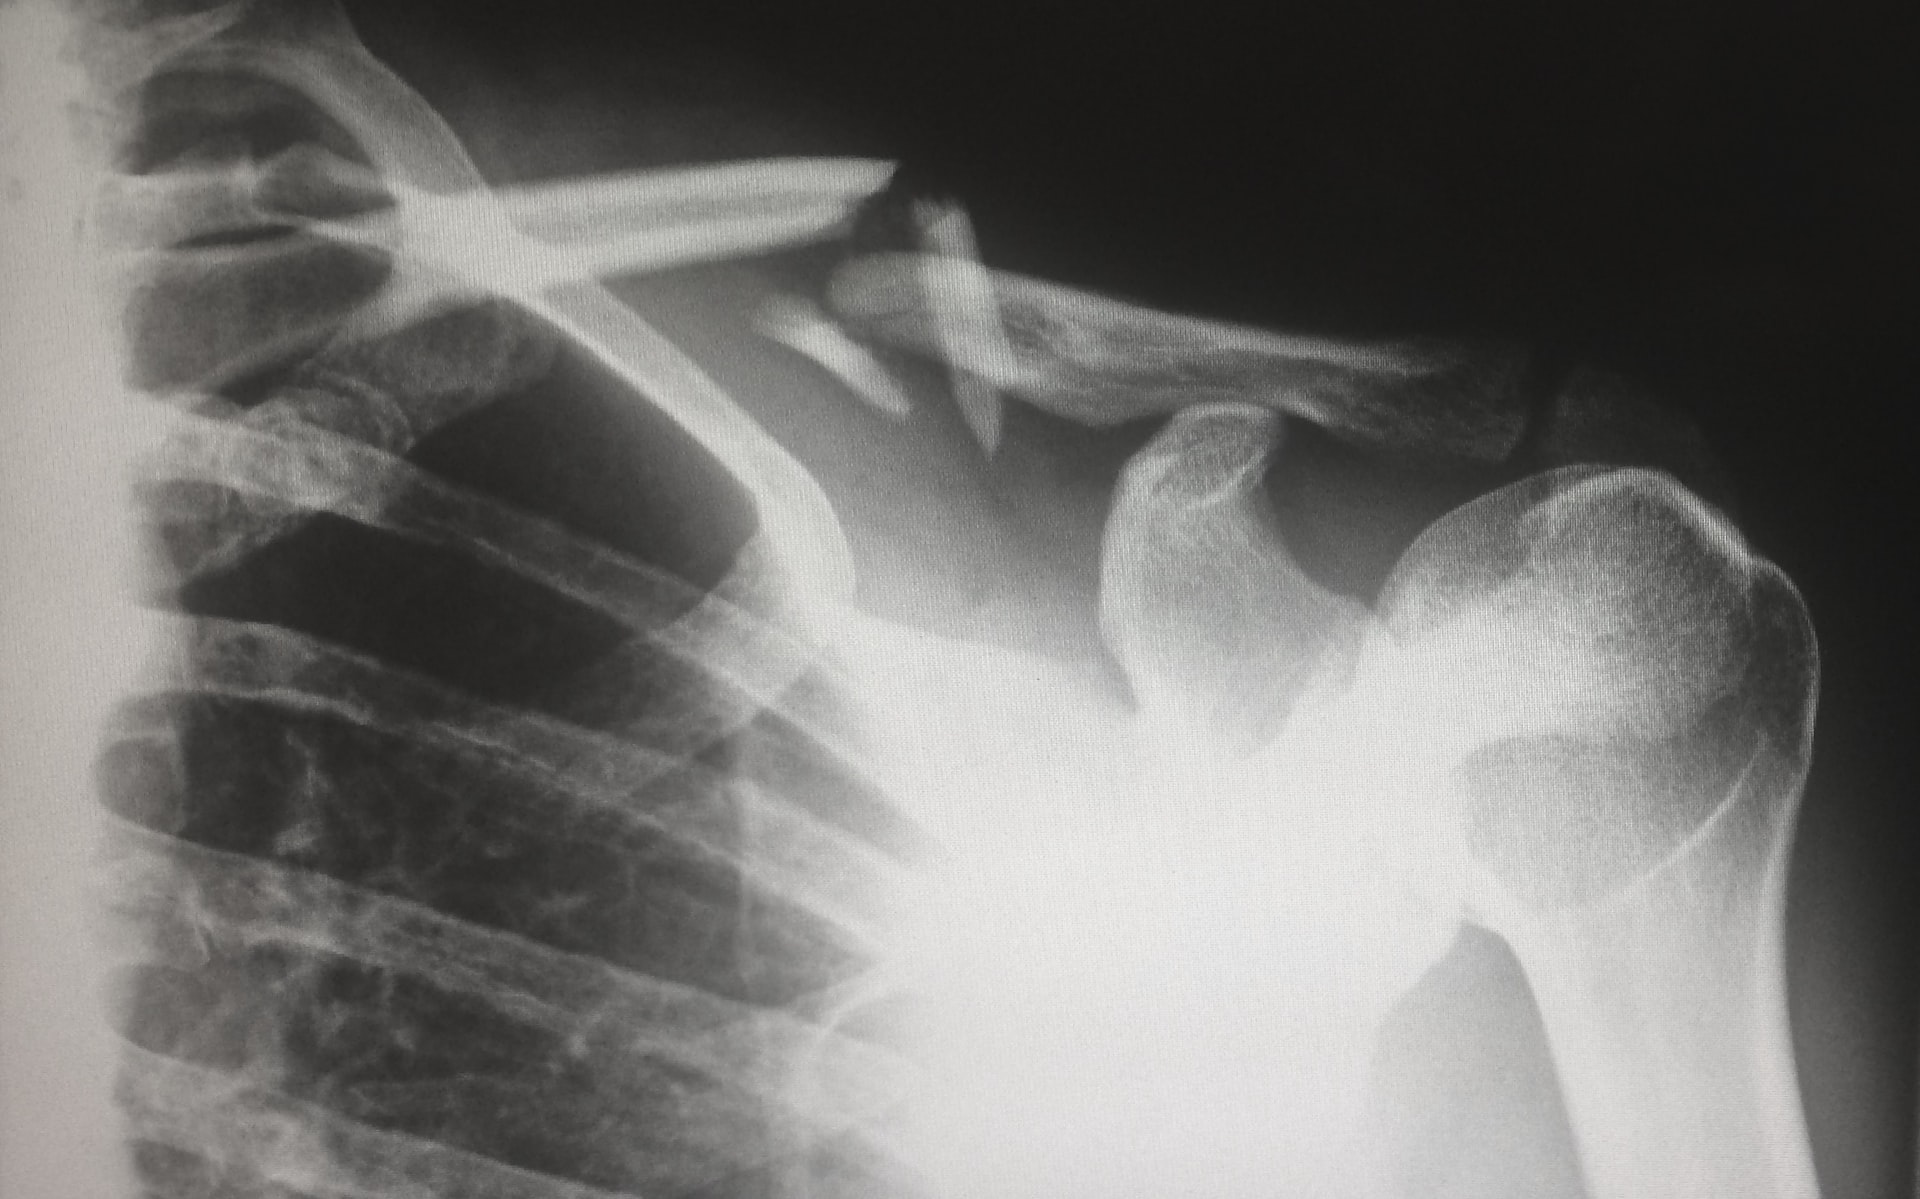

Broken Shoulder Bones

During a fall, it isn’t uncommon for the shoulder, hips and knees to take the brunt of the impact. Curling up your arms around your head to protect it often result in more force hitting the shoulders than the knees. In other cases, the person reaches out to catch themselves and fails to do so, so the shoulder takes the brunt of the trauma. This is why shoulder dislocations are common during slips and falls can also cause broken clavicles and collar bones.

Note that shoulder injuries often accompany neck injuries. These can range from muscle sprains to broken vertebrae, and this can result in anything from pain to paralysis. Every neck and shoulder injury is painful.